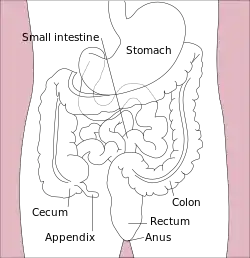

In the latter stages of human digestion, ingested materials are inundated with water and digestive fluids such as gastric acid, bile, and digestive enzymes in order to break them down into their nutrient components, which are then absorbed into the bloodstream via the intestinal tract in the small intestine. Prior to defecation, the large intestine reabsorbs the water and other digestive solvents in the waste product in order to maintain proper hydration and overall equilibrium.[25] Diarrhea occurs when the large intestine is prevented, for any number of reasons, from sufficiently absorbing the water or other digestive fluids from fecal matter, resulting in a liquid, or "loose", bowel movement.[26]